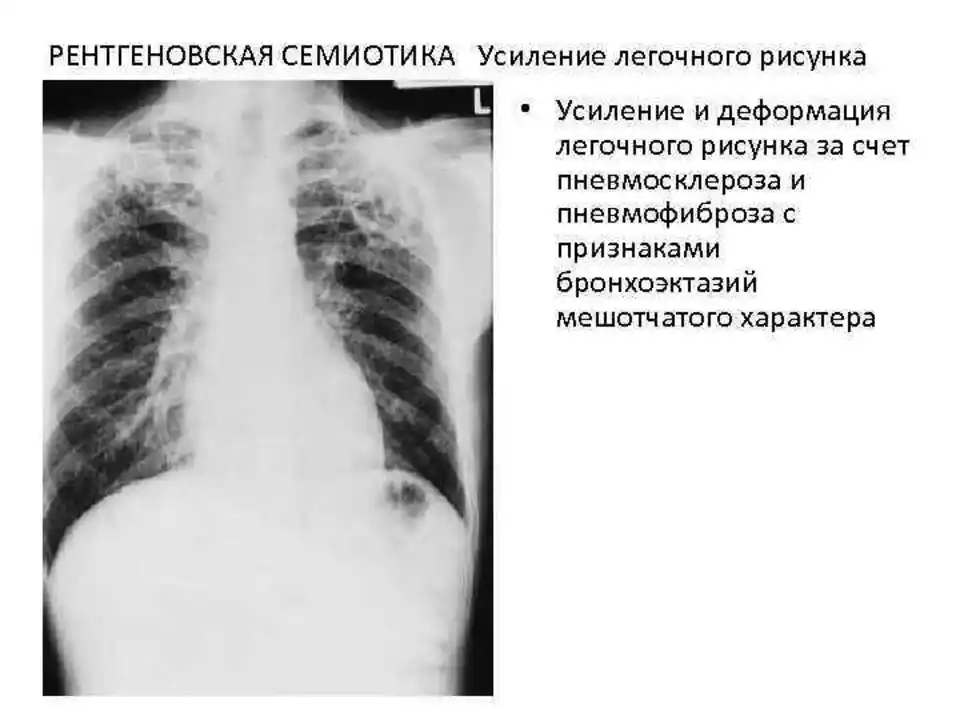

Фотографии, демонстрирующие обнаруженное усиление легочного рисунка

Раздел: Фотодневник открытий